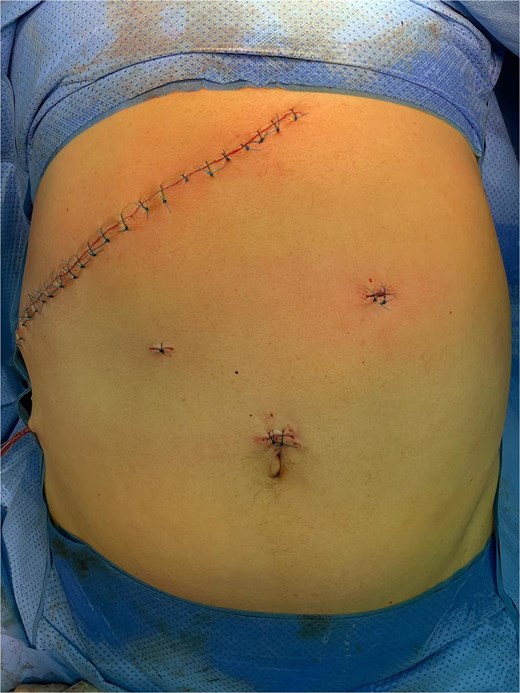

The initial laparoscopic approach was converted to right subcostal laparotomy (Fig. 2) due to unfavorable local conditions and severe inflammatory changes.